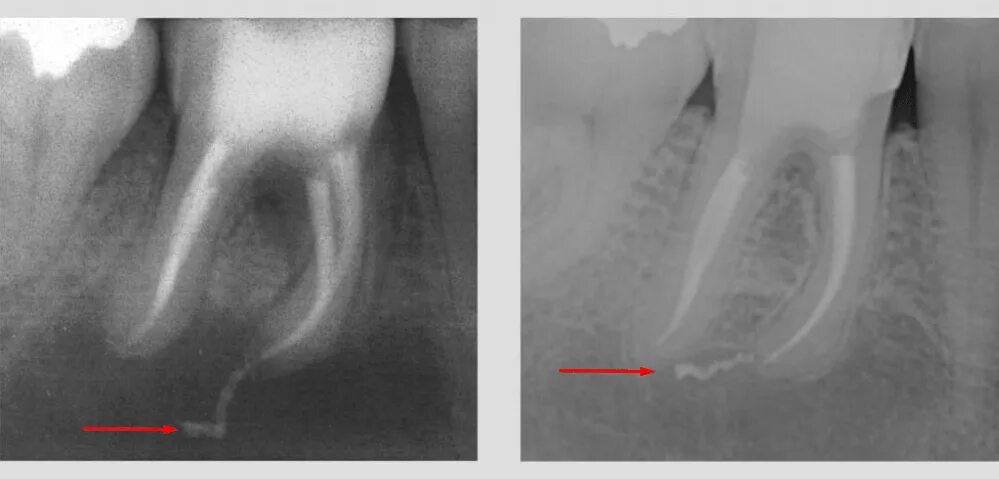

Удалить нервы запломбировать